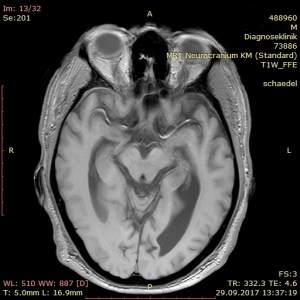

Doch nicht nur die Kinderseele wird durch Missbrauch und Misshandlung langfristig zerstört, sondern auch der Körper und der Sitz der Psyche, das Gehirn. Es ist längst bekannt, dass sexualisierte Gewalt, Misshandlung und Deprivation die Gehirnentwicklung von Kindern massiv beeinträchtigt. Insbesondere sind es Amygdala und Hippocampus, die sich auffällig verändern.

In der Amygdala werden insbesondere stressbedingte Erinnerungen abgelegt. Sie ermöglicht es uns, bei Gefahr sofort, gleichsam instinktiv, zu handeln. Sie setzt den Impuls für Flucht oder Angriff, noch ehe wir in der Gefahr einen entscheidenden Gedanken fassen konnten. Bei erfolgtem Missbrauchserleben ist die Amygdala häufig vergrößert. Anders hingegen der Hippocampus, der die Gedächtnisleistung zwischen Kurz- und Langzeitgedächtnis koordiniert und auch unsere Empfindungsfähigkeit reguliert; er reduziert sich unter dauerhaftem Disstress. Beide Hirnregionen zählen zum limbischen System, das unsere Triebe und Emotionen insgesamt steuert. Angst, Furcht, Depression, eingeschränkte Gedächtnisleistung, emotionale Taubheit und auffälliges Sozialverhalten sind die Folgen von Störungen im limbischen System. Die hirnorganischen Ursachen einer posttraumatischen Belastungsstörung (PTBS) können hier gleichfalls lokalisiert werden.

Dieser Tage erhielt ich einen erschreckenden Einblick in das Ausmaß der Zerstörung Meinerselbst durch Vater und Mutter, die beiden Mörder meiner Seele. Auf der diagnostischen Suche nach der Ursache für meinen Schwankschwindel wurde auch mein Schädel fixiert und per MRT durchleuchtet. Nach der 25minütigen Prozedur in der Röhre traf ich den Radiologen vor dem Bildschirm und sah mir scheibchenweise ins Gehirn. Der Arzt war sichtlich betroffen über die auffällige Atrophie meines Gehirns. Er zeigte mir die ungewöhnlich ausgedehnten Ventrikel, sprich Hohlräume, an den Seiten und im Innenraum meines Brägens. Er fragte nach möglichen Erkrankungen wie Diabetes und Bluthochdruck. Ich verneinte und erwähnte meine PTBS. Er erkundigte sich nach der Ursache, ich verstand die Frage akustisch nicht, meine Frau antwortete für mich: sexueller Missbrauch und Misshandlung durch die Eltern. Nun kam zu seiner Betroffenheit noch ein tieftrauriger Zug, und er erklärte mir, dass Missbrauch und Misshandlung derlei tiefe und bleibende Spuren im Gehirn hinterlassen. Angesichts meiner geistigen Präsenz zeigte er zudem über die strukturelle Regenerationsfähigkeit des Gehirns Erstaunen. – Später sah ich im Internet das „Schalenhirn“ eines Mathematikers mit einem IQ von 126, das nur geschätzte 100 g Masse besaß (siehe hier).

In meinem Therapietagebuch notierte ich dazu trocken: „Neben dieser Diagnose: keine Blutungen, keine Aneurysmata, keine Tumore oder Metastasen. Nur ein weiterer Ausschluss auf der Diagnose zum psychogenen Schwankschwindel. Die Hirnatrophie selbst ist nur ein Sachverhalt des Missbrauchs, man kann auch mit einem „Resthirn“ gescheit und sinnenfroh überleben.“

kurz zu ihren schnittaufnahmen vom kopf. ich bin kein fachmann und kann damit nicht viel anfangen, obwohl ich vor vielen jahre einem oberarzt erklären musste, wir er mit schnittaufnahmen umzugehen hat. er sagte über die aufnahmen unseres jüngsten den ermutigenden satz: aber der hat ja kein gehirn. – ich habs ihm dann gezeigt. unser jüngstes kind, ein adoptivkind, kam mit einem hirnschaden zur welt, dazu gehörte der hydrozephalus (wasserkopf). ganz beiläufig hatte ich im psychologie-studium gelernt, dass man auch mit hydrozephalus beachtliche leistungen erbringen kann.

viele jahre später, bei einer shuntkontrolle, sagte der professor vor dem lichtkasten, einen oberarzt neben sich: schauen sie sich das bild an. unsereins wäre halbseitig gelähmt, der aber spielt geige und braucht dazu die finger der linken hand. merken sie sich: immer wenn sie ein bild sehen und das kind daneben, und das stimmt nicht überein, dann hat das kind recht.